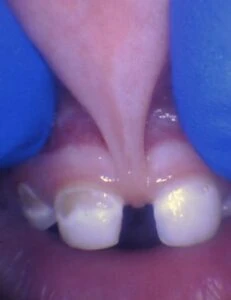

IMAGES OF TONGUE- AND LIP-TIES

Spectrum of lip restriction in a child

Spectrum of tongue restriction in a child

Posterior tongue-tie in a child seen with lifting the tongue. The posterior or “hidden”tongue-tie can cause the same symptoms including nursing pain and poor weight gain, as a to-the-tip tie in a child